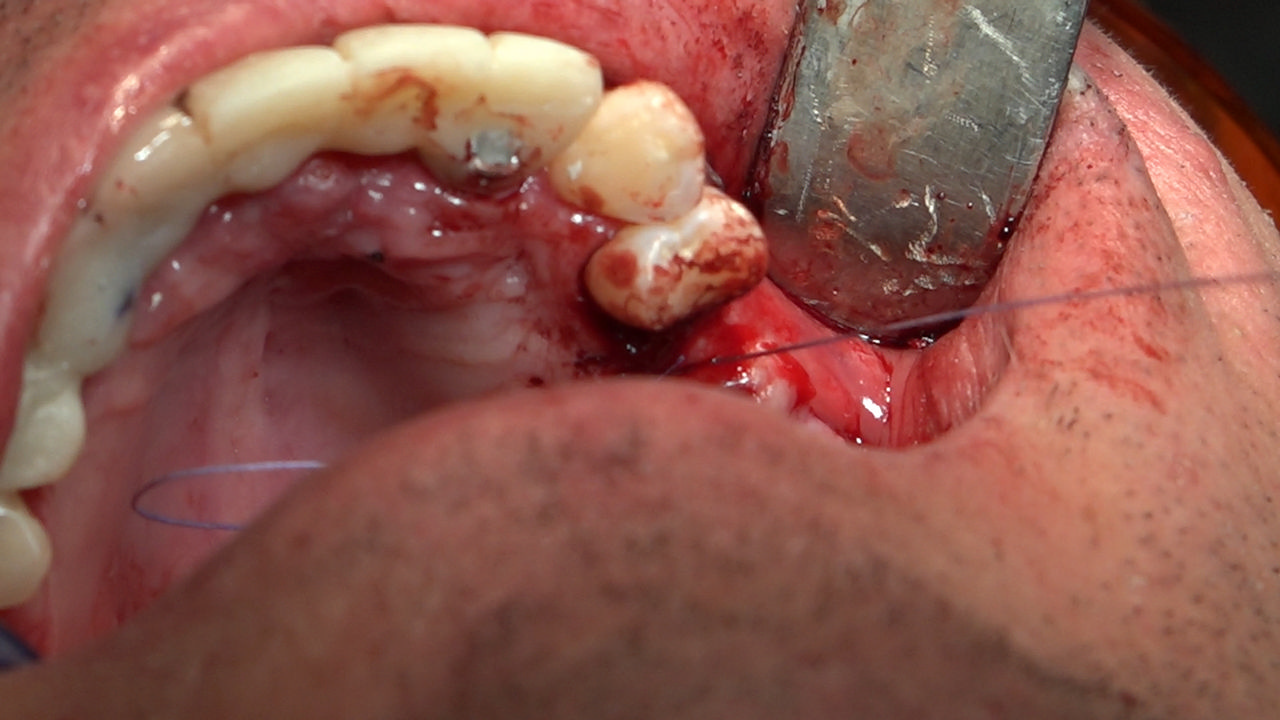

7 Sesja X Sezonu Practiculum Implantologii, w której brali udział kursanci z Grupy A i B, obejmowała implantacje wykonane systemem Axiom, procedury regeneracyjne tkanki kostnej i zabieg sinus lift oraz procedury implantoptotetyczne. Ten zakres szkolenia poprowadziła dr Małgorzata Piotrowska. Protetyka na implantach, to finalny etap leczenia implantologicznego decydujący o uzyskaniu harmonijnego łuku zębowego, okluzji oraz szczelności połączeń, a więc zadowoleniu Pacjenta i powodzeniu całego procesu leczenia.

Jego sednem jest wybór optymalnego rozwiązania rekonstrukcji protetycznej uwzględniający bardzo wiele czynników o charakterze mechanicznym, funkcjonalnym i estetycznym, związanych ze stanem tkanki kostnej, jamy ustnej i uzębienia. Odbywa się już na etapie tomografii komputerowej i jest ściśle powiązany z częścią chirurgiczną, ponieważ prawidłowe zaplanowanie pracy i usytuowania implantów wspomagane plastyką tkanek miękkich, to dla procedur protetycznych baza wyjściowa. Zasady te są jak najbardziej oczywiste, zarówno przy samodzielnym wykonywaniu leczenia implantologicznego, jak i przy podziale zadań dla chirurga i protetyka, czyli pracy w duecie.